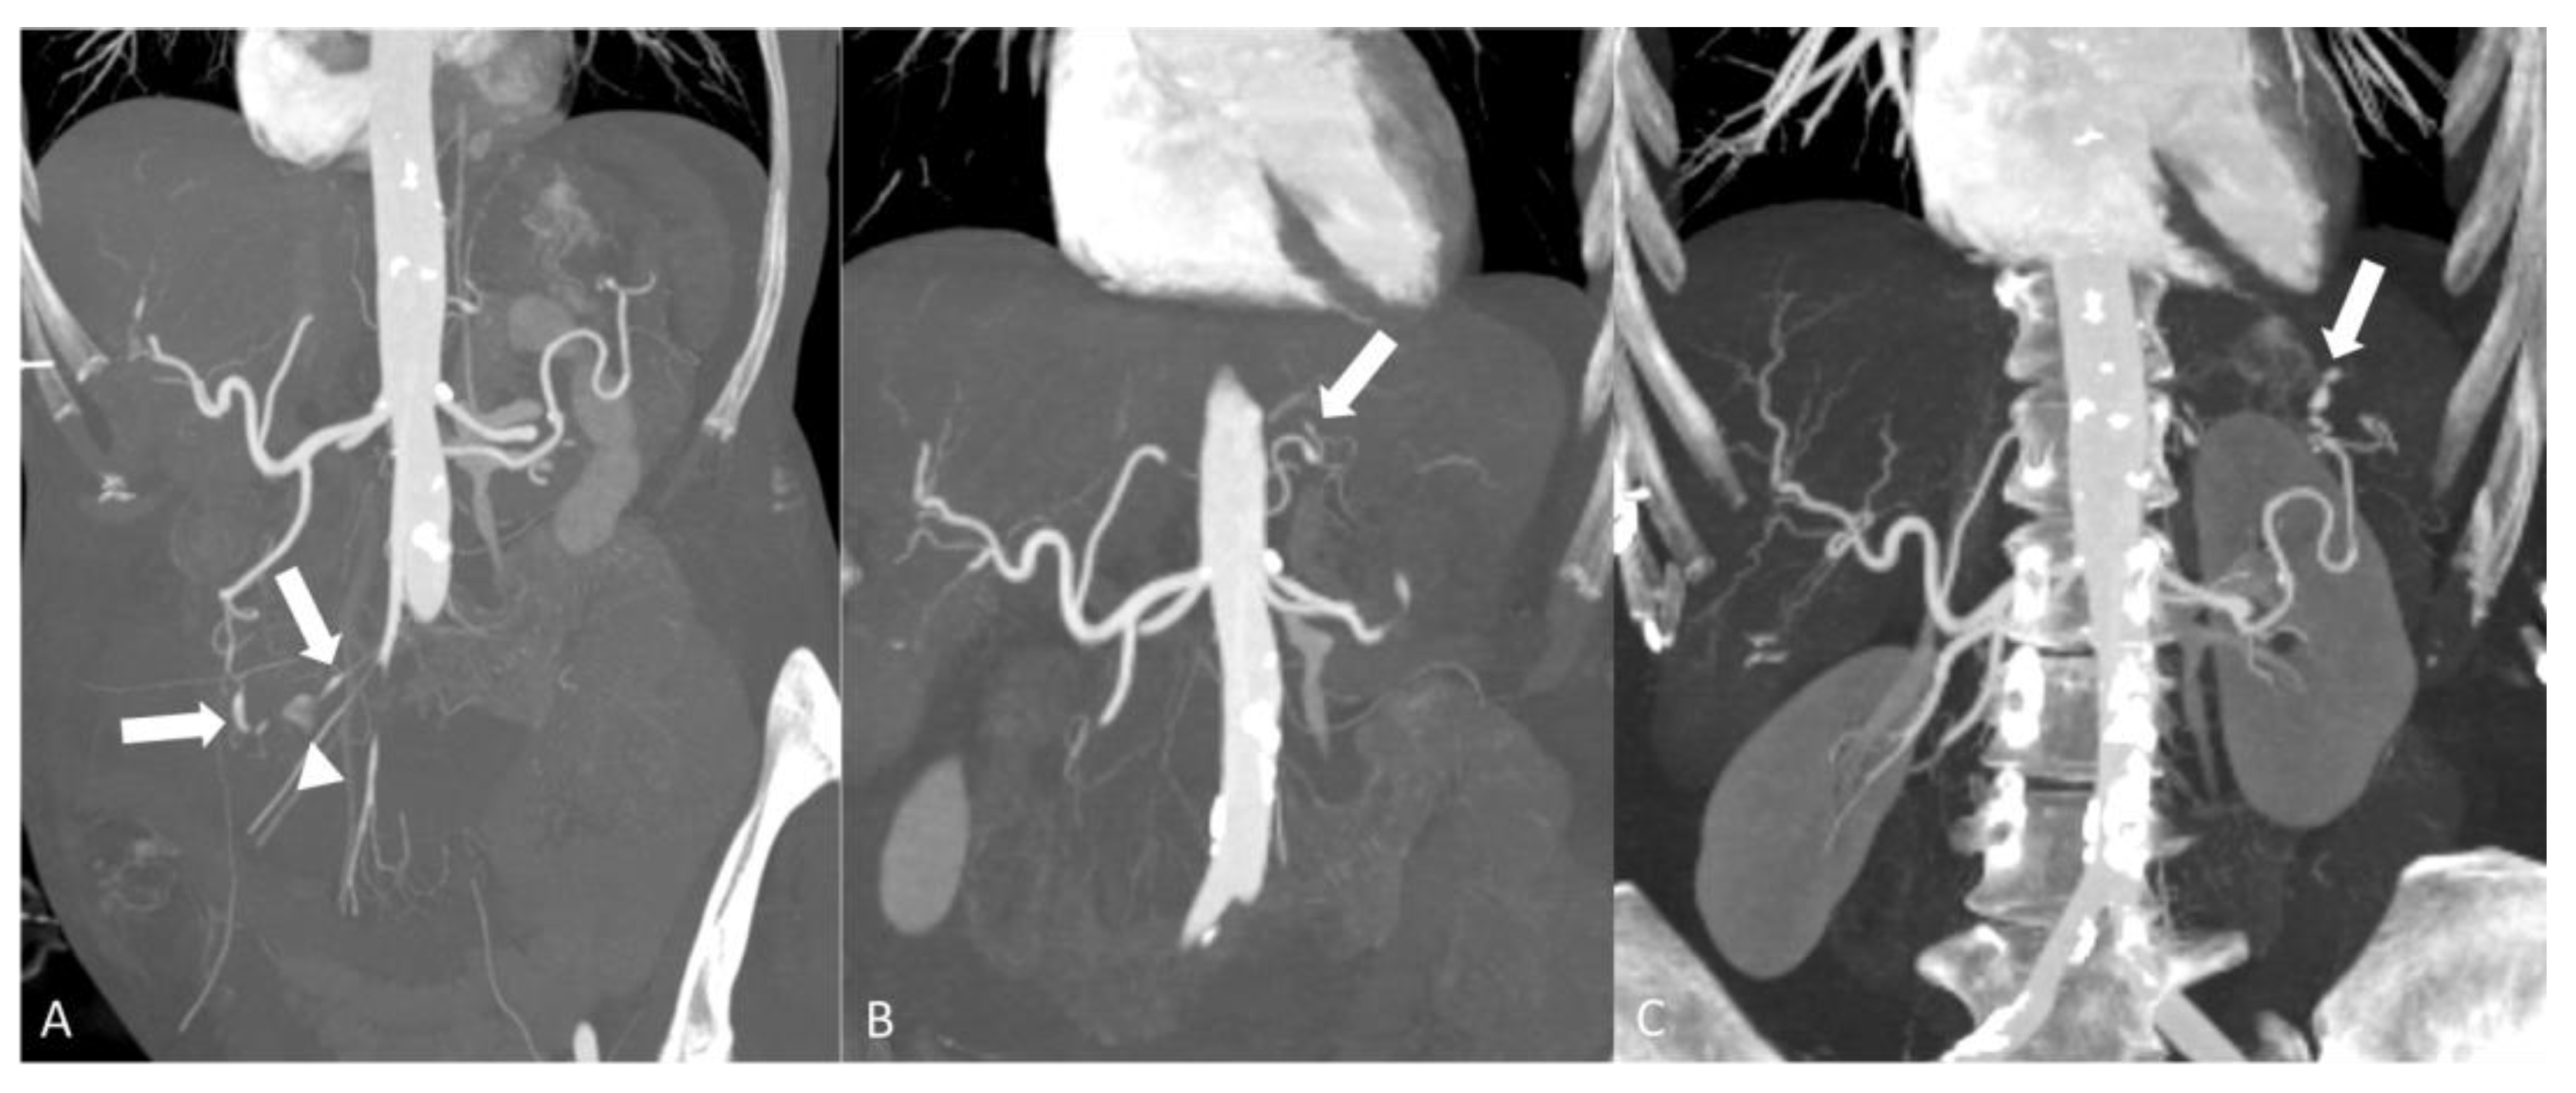

2.1.2. Takayasu’s Arteritis

- Barra, L.; Kanji, T.; Malette, J.; Pagnoux, C. Imaging modalities for the diagnosis and disease activity assessment of Takayasu’s arteritis: A systematic review and meta-analysis. Autoimmun. Rev. 2018, 17, 175–187. [Google Scholar] [CrossRef] [PubMed]

- Papa, M.; Cobelli, F.D.; Baldissera, E.; Dagna, L.; Schiani, E.; Sabbadini, M.; Maschio, A.D. Takayasu Arteritis: Intravascular Contrast Medium for MR Angiography in the Evaluation of Disease Activity. Am. J. Roentgenol. 2012, 198, W279–W284. [Google Scholar] [CrossRef]